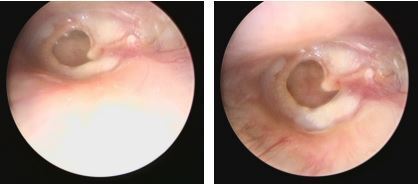

最近遇到一些關(guān)于鼓膜穿孔的爭(zhēng)論,醫(yī)患的角度不同,理解不同,醫(yī)生可以很理性,而患者牽涉自身,往往很感性。非常理解,但是知識(shí)相通才可以構(gòu)建交流的橋梁。所以,關(guān)于鼓膜穿孔這件事兒,想給大家普及一點(diǎn)知識(shí),以便大家可以理性健康的對(duì)待我們的耳朵??耳從解剖角度分外耳、中耳及內(nèi)耳,鼓膜位于外耳道底部,與外耳道有一個(gè)大約45度的夾角,鼓膜的主要作用是聲波傳導(dǎo)作用,由于鼓膜的解剖位置及外耳道與中耳腔微生物環(huán)境的不同,鼓膜也有分界外中耳,起到楚河漢界的作用。最常見的鼓膜穿孔的因素有兩類,一類是耳外傷,另一類是急性炎癥。耳外傷常見的有不良挖耳習(xí)慣損傷,比如掏耳朵不慎棉簽捅入鼓膜導(dǎo)致?lián)p傷,此外,還有打架耳光損傷以及一些重大交通事故損傷。另一類導(dǎo)致鼓膜穿孔的因素多為感染,急性上呼吸道感染后引發(fā)急性中耳炎,耳痛劇烈,流膿,流膿后耳痛減輕。尤其是在兒童期,夜間發(fā)熱、耳痛,急診檢查鼓膜充血紅腫,用藥一兩天發(fā)現(xiàn)耳道內(nèi)多量血性分泌物,大多為急性炎癥刺激導(dǎo)致鼓膜穿孔,檢查可以見到鼓膜表面有光點(diǎn)波動(dòng)—俗稱燈塔征,是中耳膿性分泌外涌的表現(xiàn)。亦有部分反復(fù)發(fā)作的慢性外耳道炎患者,多有不良掏耳習(xí)慣,反復(fù)挖耳或者清理沖洗,炎癥初始分布外耳道,后進(jìn)一步波及鼓膜,導(dǎo)致鼓膜表面有炎癥滲出及肉芽生長(zhǎng),鼓膜菲薄,外力作用或炎癥進(jìn)一步刺激,可導(dǎo)致鼓膜穿孔。鼓膜的生理作用為傳音、分界外中耳的作用,當(dāng)發(fā)生鼓膜穿孔后,鼓膜的傳音作用受到影響,故而多數(shù)穿孔患者都有一定程度的聽力損失。國(guó)內(nèi)外學(xué)者的研究顯示:穿孔越大,聽力損失越重。大部分鼓膜穿孔都有25-40分貝左右的聽力損失,當(dāng)然,鼓膜穿孔導(dǎo)致的聽力下降,也與中耳容積及中耳粘膜的狀態(tài)有關(guān)系。此外,由于外中耳的楚河漢界被破壞,外耳道與中耳腔相通,外源性的感染因素可以直接進(jìn)入中耳,導(dǎo)致中耳炎的發(fā)生。同時(shí),中耳腔被覆粘膜組織,而外耳道是上皮為主,兩者在酸堿度及濕度上均有不同,外中耳交通,易導(dǎo)致外耳道炎癥的發(fā)生。外傷因素導(dǎo)致的鼓膜穿孔,多為裂隙狀、不規(guī)則形穿孔,治療上要求患者保持外耳干燥、禁用滴耳液,適當(dāng)抗炎預(yù)防感染,大多數(shù)外傷性鼓膜穿孔多在兩周到一個(gè)月左右愈合,如果超過三個(gè)月沒有愈合,考慮外傷性鼓膜穿孔無法自愈,就需要進(jìn)一步手術(shù)干預(yù)。穿孔的愈合過程為鼓膜表面上皮向?qū)?cè)爬行的過程,最終會(huì)使不規(guī)則形狀的穿孔愈合。上皮爬行過程可使鼓膜穿孔相鄰邊緣愈合,上皮進(jìn)一步向內(nèi)側(cè)爬行,由不規(guī)則的穿孔,變?yōu)閳A形、橢圓形、腎形或者馬蹄形。故而,慢性反復(fù)發(fā)作的中耳炎,多難自愈,其穿孔也多為近圓形、橢圓形或腎形的。穿孔的病理狀態(tài)存在,使中耳腔不定期處于感染狀態(tài),或有反復(fù)流膿的,也有炎癥過度反應(yīng),使鼓室內(nèi)粘膜玻璃樣變性,進(jìn)而進(jìn)一步導(dǎo)致聽力下降,這就是中耳炎最常見的并發(fā)癥--鼓室硬化。故而,對(duì)于鼓膜穿孔的患者,建議患者選擇合適的時(shí)機(jī),行手術(shù)修補(bǔ)。

最近來自佛山的曾女士找到耳鼻喉鄭立崗醫(yī)生,1天前她去采耳后出現(xiàn)右耳痛,耳堵塞感,聽力下降,耳膜。我檢查檢查后發(fā)現(xiàn)右側(cè)鼓膜穿孔了,估計(jì)是采耳的時(shí)候由于技師的操作不熟練導(dǎo)致的。做了耳內(nèi)鏡檢查后發(fā)現(xiàn)確實(shí)是右側(cè)鼓膜中等大小的穿孔,這種情況需要先觀察看看,如果自己能長(zhǎng)好那是最好的情況。如果觀察一段時(shí)間好不了就需要做耳內(nèi)鏡微創(chuàng)手術(shù)了。對(duì)于采耳的問題,耳鼻喉鄭立崗醫(yī)生一直建議大家對(duì)耳朵的最好保護(hù)就是盡量的不要掏耳朵。能不采耳盡量的還是不要采耳,如果耳朵堵塞發(fā)炎了,還是首選來耳鼻喉科做個(gè)耳內(nèi)鏡要更加的安全一些。關(guān)于鼓膜穿孔,如果您還有什么問題,歡迎留言和耳鼻喉鄭立崗醫(yī)生進(jìn)一步交流。